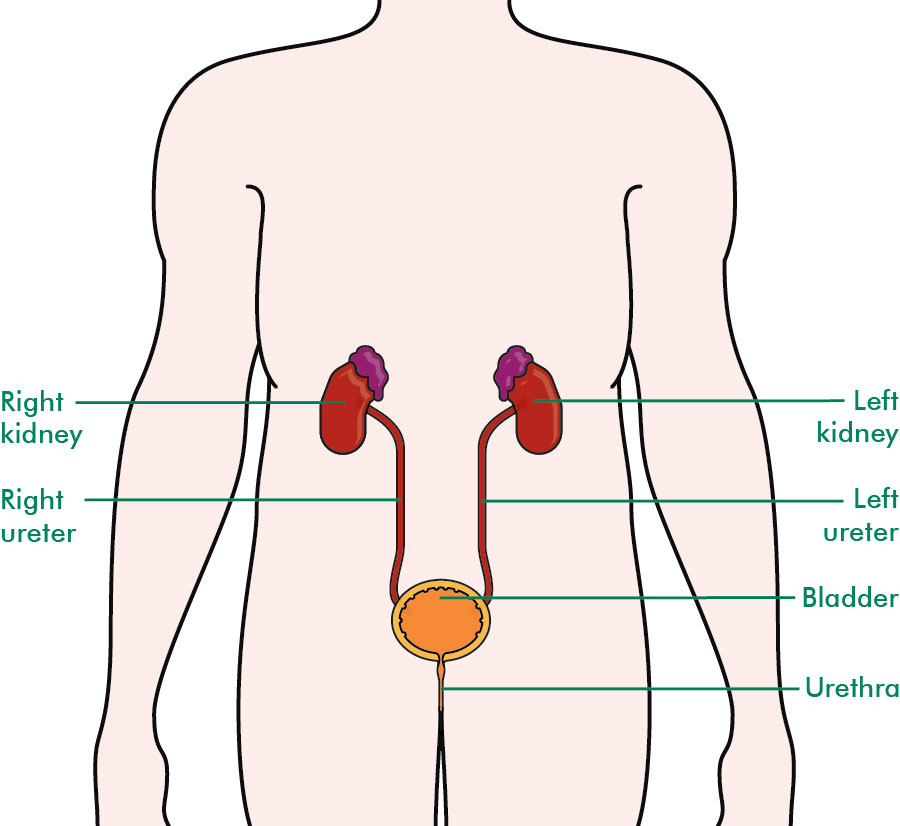

location of the bladder in the human body

Posts: location of the bladder in the human body